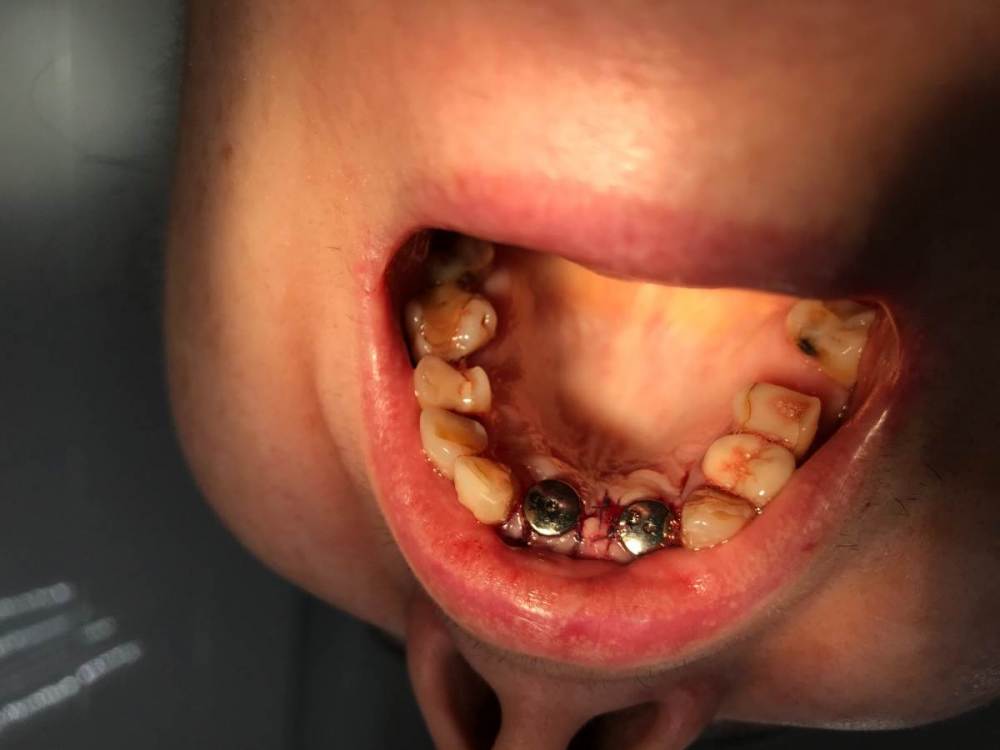

MakovskyAlexandr Опубликовано 8 октября, 2020 Поделиться Опубликовано 8 октября, 2020 Здравствуйте, люди добрые, подскажите пожалуйста.Удалены 2 Корня(21 и 12). Пациентка отказалась от трёх коронок, изъявила желание именно двумя восстановить.Удалены корни - установлены импланты анкилоз А3.5 11 и 14 мм.Выполнена костная пластика , материал ограждён мембраной- все по классике, мембрана фиксирована пинами. Я так понимаю произошло смещение материала( то от гематома, то ли отёк такой). Как быть дальше? Ждать интеграции и подсаживать потом аутотрансплантат?Спасибо огромное. Ссылка на комментарий

Александр07 Опубликовано 31 октября, 2020 Поделиться Опубликовано 31 октября, 2020 Здравствуйте, люди добрые, подскажите пожалуйста.Удалены 2 Корня(21 и 12). Пациентка отказалась от трёх коронок, изъявила желание именно двумя восстановить.Удалены корни - установлены импланты анкилоз А3.5 11 и 14 мм.Выполнена костная пластика , материал ограждён мембраной- все по классике, мембрана фиксирована пинами. Я так понимаю произошло смещение материала( то от гематома, то ли отёк такой). Как быть дальше? Ждать интеграции и подсаживать потом аутотрансплантат?Спасибо огромное.Похоже мембрана плохо запинена была, если ничего не беспокоит я бы не трогал, пусть не давит туда и не трогает вообще, если прорезаться материал начнёт или ещё что тогда удалите Ссылка на комментарий

MakovskyAlexandr Опубликовано 13 ноября, 2020 Автор Поделиться Опубликовано 13 ноября, 2020 Сколько прошло после имплантации? есть фото? Швы разошлись?Прошёл уже месяц. Нет ничего не разошлось, все зажило, швы давно сняты.Как придёт на приём сфотографирую и скину фото. Ссылка на комментарий